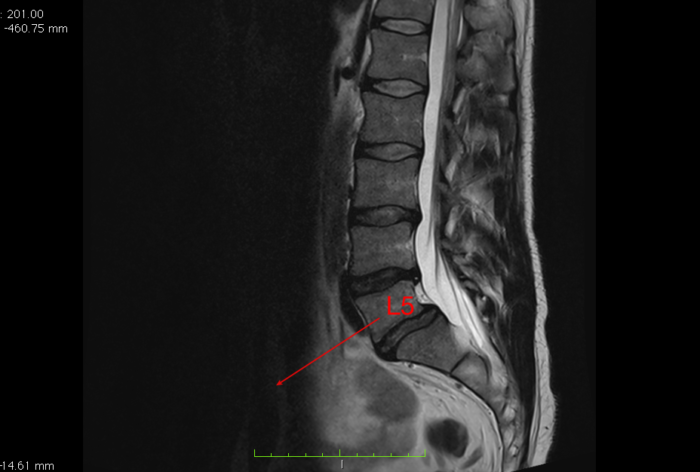

Bardzo zaawansowany strukturalnie kręgozmyk L5-S1 (II/III stopień), dający pacjentowi niewielkie dolegliwości bólowe oraz znikome objawy neurologiczne.